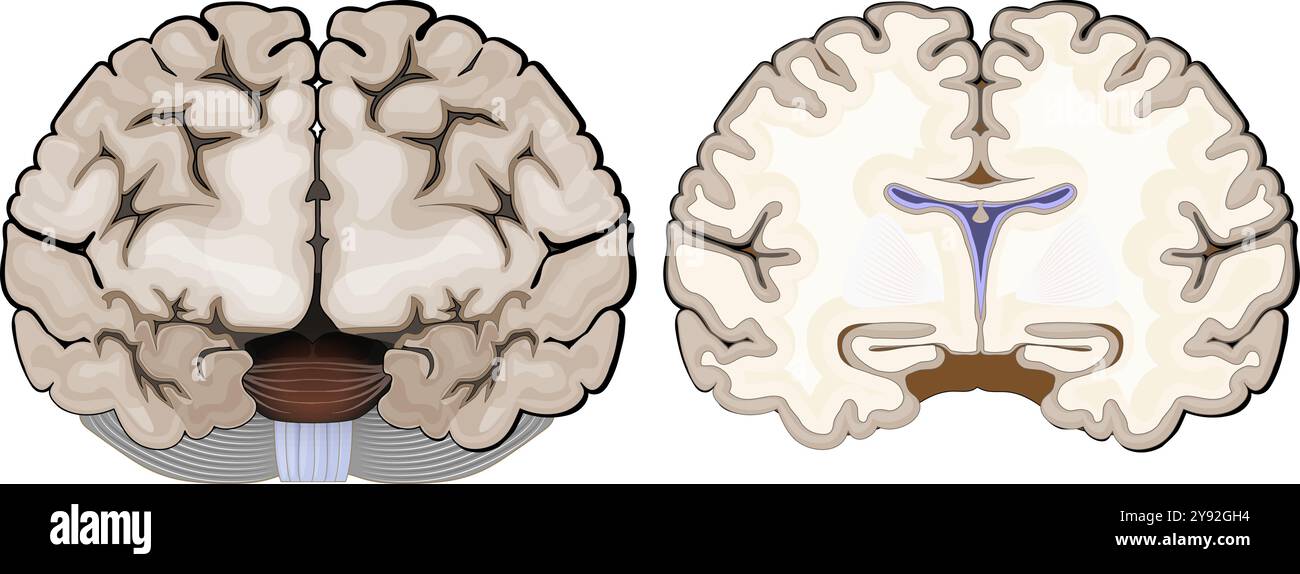

RF2XHY7B8–Anatomia cerebrale. Materia bianca e materia grigia. Corteccia cerebrale e ventricoli cerebrali con liquido cerebrospinale. Sezione trasversale di una vista frontale del cervello umano

RF2Y92GH4–Anatomia cerebrale. Vista frontale e sezione trasversale di un cervello umano. Primo piano dell'Hippocampus e dei ventricoli. Corteccia cerebrale. Illustrazione vettoriale